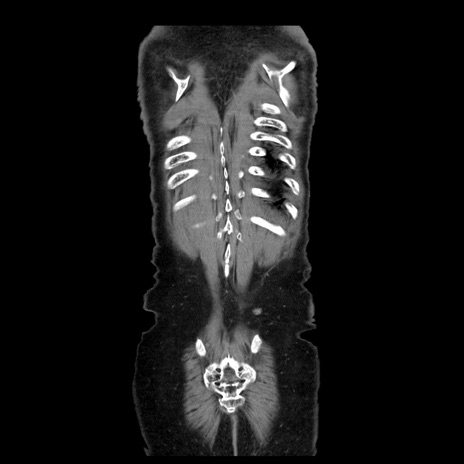

横断像